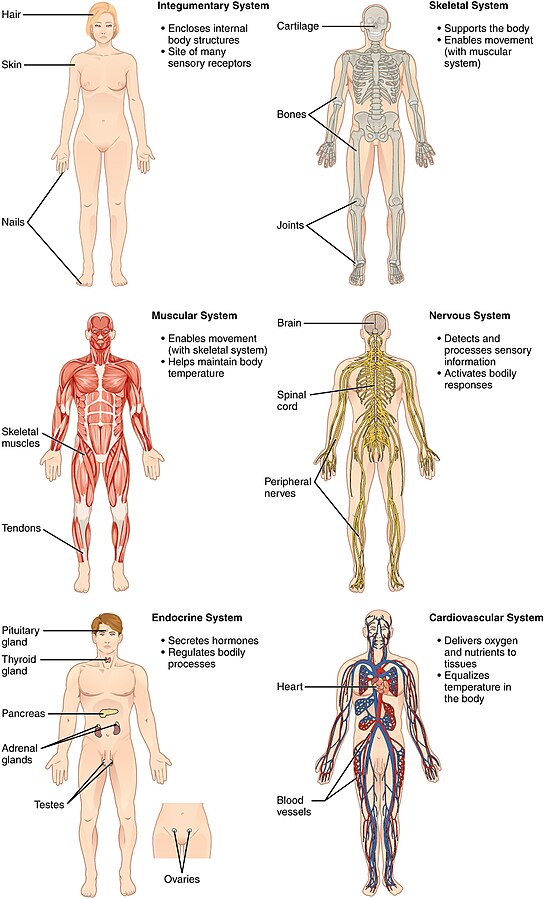

شکل دوم شکم مادری را نشان می دهد که جنین دختر دارد. وحشت مادر از عکس سونوگرافی جنین داخل شکمش عکس. تصاویر جالب از داخل مغز و نخاع انسان آخرین نیوز. بدن انسان کل ساختار انسان است که سر گردن تنه سینه و شکم دو بازو و دست ها و دو ساق پا و پاها را شامل می شود.

رونمایی از جرد لتو در نقش جوکر عکس. این تصاویر عجیب و بی نظیری كه مشاهده می کنید مربوط به یك ساختمان واقع در كشور هلند است كه شبیه انسان ساخته شده و از تاریخ چهاردهم مارس 2008 برای بازدیدكنندگان فعال بوده است. فرم شکم زنان باردار دختر. هر قسمت بدن از انواع مختلف سلول تشکیل شده است.

به گفته مایک جنس استخوان دنبالچه آخرین بقایای دم انسان است و جالب تر اینکه تمام پستانداران دنیا در شکم مادر دم دارند و فقط انسان است که قبل از تولد ان را از دست می دهد.